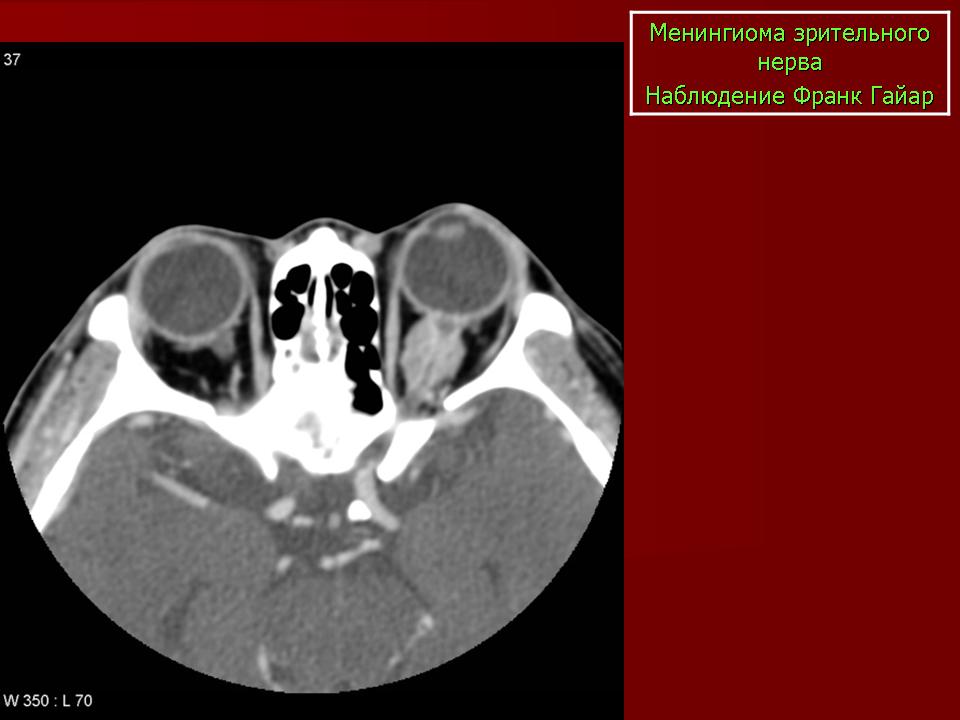

КТ-семиотика

На КТ срезах без контрастного усиления менингиома зрительного нерва выглядит изоденсной. Типично наличие линейных или точечных обызвествлений. Симптом «трамвайных рельс» отражает накопление КВ по сторонам гиподенсного зрительного нерва или наличие обызвествлений в структуре опухоли. Как правило, наиболее дистальная часть зрительного нерва, в месте его вхождения в глазное яблоко, не содержит обызвествлений.

При исследовании необходимо определить расположение бляшковидной менингиомы относительно бугорка турецкого седла и пластинки клиновидной кости, так как данный тип опухоли может распространяться интракраниально через канал зрительного нерва. КТ не позволяет адекватно визуализировать интракраниальное распространение опухоли, которое может привести к развитию двусторонней слепоты.